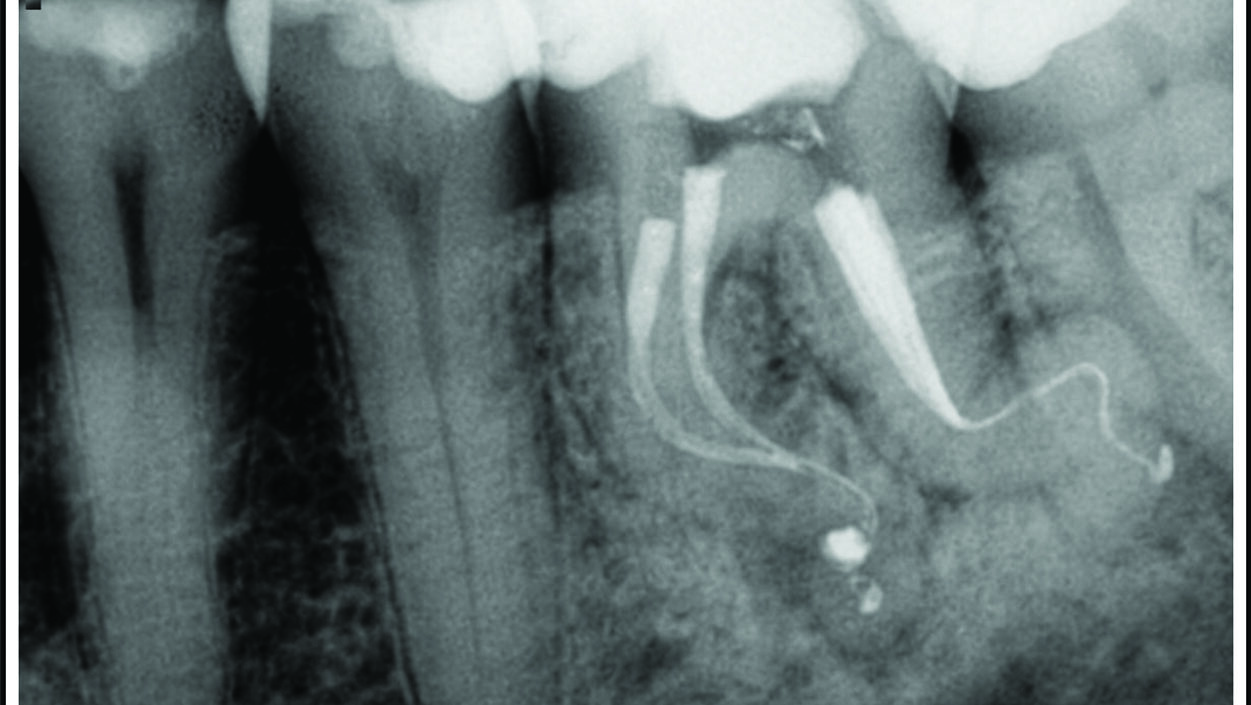

Deep Shape in Endodontics: Significance, Rationale and Benefit

The goal of endodontic treatment is to prevent or cure, when present, Lesions of Endodontic Origin, at times referred to as apical periodontitis. The role of bacteria in the pathogenesis of endodontic disease is well established, and therefore, it is critical to eradicate these pathogens by employing the highest level of presently developed standards. This … Read more